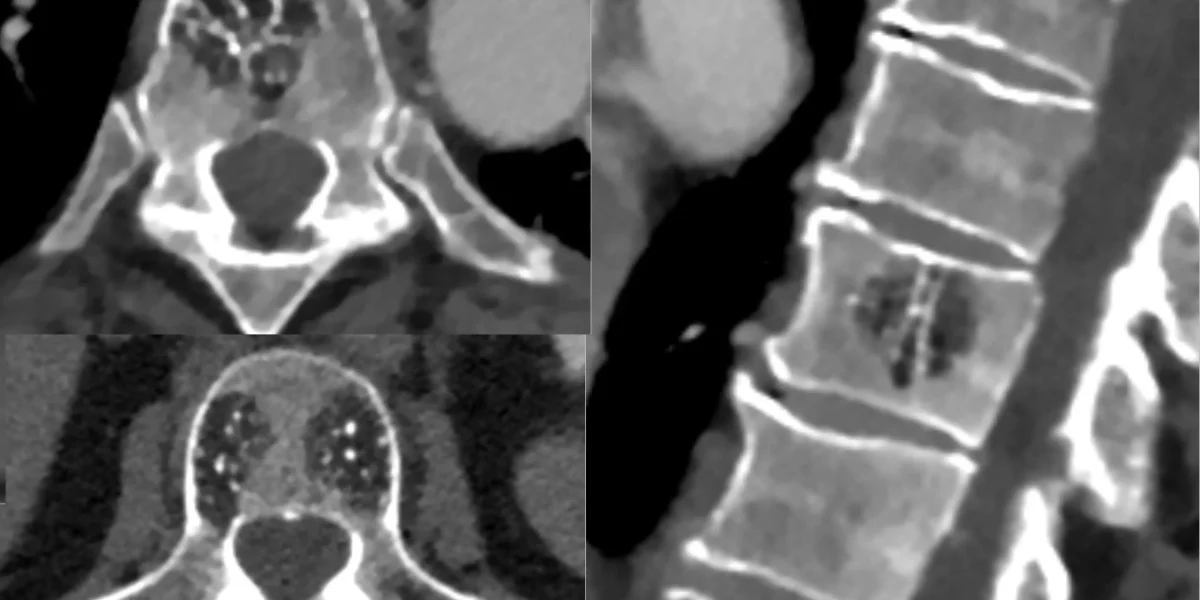

CT scans showcasing Hemangioma Spine

The size, location, and level of lytic involvement of the spinal canal and neural foramina are all important factors to consider when evaluating a hemangioma. A pronounced trabecular pattern with vertical striations is typically visible on radiographs. The vertebral body’s density is frequently increased, giving it a sclerotic appearance. The height and size of the vertebral bodies should not change. Hemangiomas exhibit the well-known corduroy (accordion) pattern on CT scans due to the coarsening of the trabeculae. Despite being uncommon, CT imaging can be used to assess bone damage and extension into nearby soft tissues, such as the spinal canal. MR imaging offers a conclusive evaluation of soft tissue extension.